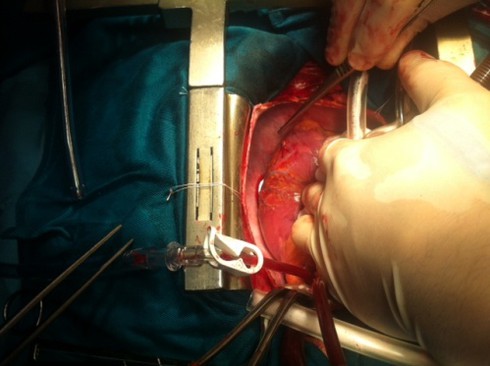

Theo PGS-TS Ước, để phẫu thuật lấy dị vật cho bệnh nhân, các bác sĩ đã quyết định làm liệt tim, chạy máy thở nhân tạo cho bệnh nhân, sau đó mở tim, cầm máu. Khi phẫu thuật mở vùng tim ra, một góc của tim đã bị tổn thương nặng nề do tim co bóp mạnh, chiếc kim bị đẩy đi đẩy lại nhiều lần.

Sau 2 giờ phẫu thuật, các bác sĩ đã lấy ra được cây kim dài 4,5 cm ra khỏi tim của bệnh nhân. Sau mổ, sức khỏe bệnh nhân dần ổn định nhưng vẫn cần được theo dõi chặt chẽ. Dự kiến khoảng 1 tuần sau, bệnh nhân mới có thể xuất viện.

| Các bác sĩ tiến hành phẫu thuật cho bệnh nhân. Ảnh do bác sĩ cung cấp |